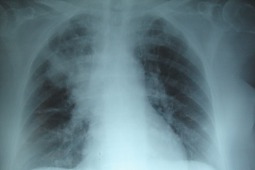

W badaniu head-to-head wzięło udział 60 chorych z uogólnioną postacią TU (anty-Scl-70 pozytywni) z zajęciem skóry i potwierdzonym w badaniu HRCT i badaniach czynnościowych zajęciem płuc. Chorych losowo przydzielono do jednej z dwóch grup – w jednym z ramion badania stosowano CF w dawce 500mg/m2 p.c. we wlewach dożylnych podawanych co miesiąc, w drugim RTX podawany według protokołu 1000mg w dniach 1. i 15. Pierwotny punkt końcowy badania stanowiła ocena FVC(%) po 6 miesiącach (24 tydzień). Drugorzędowy punkt końcowy stanowiła ocena po 6 miesiącach: zmiany w zakresie FVC(L), ocena zmian skórnych w zmodyfikowanej skali Rodnana (mRSS), test 6-minutowego marszu (6-MWT), wskaźnik Medsgera oraz wystąpienie lub pogorszenie istniejącego nadciśnienia płucnego ocenianego kryteriami echokardiograficznymi. Średnia wieku w badanej populacji wynosiła 36 lat, a czas trwania choroby 24 miesiące. Średnia dawka kumulacyjna CF wynosiła w przeliczeniu na pacjenta 3,9g. W obu grupach u 25 spośród 30 chorych wykazano ponad 20% zajęcie płuc w badaniu HRCT. Obraz zmian śródmiąższowych w HRCT obejmował – niespecyficzne śródmiąższowe zapalenie płuc u 48/60, włókiennie/ obraz plastra miodu u 2/60, oraz typ mieszany u 10/60.